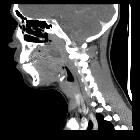

CT

- rim-enhancing fluid collection adjacent to an enlarged and inflamed tonsil

- 75% specific and 100% sensitive at diagnosing peritonsillar abscess

- false positives are due to the similar appearances of peritonsillar abscess and phlegmon